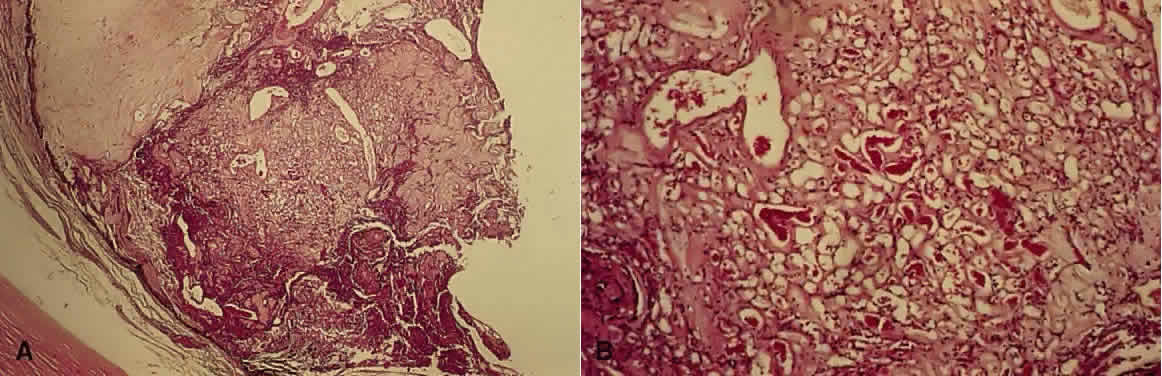

The characteristic retinal lesion in this disease is a capillary hemangioma (hemangioblastoma), composed of blast-like vascular endothelial cells and pericytes, along with foamy cells that contain lipid (Figs. 3 and 4).26,27 The origin of these foamy cells has been controversial.28 Recent work has shown that they are the true neoplastic component of the hemangioblastoma. Von Hippel-Lindau angiomatosis is inherited as an autosomal dominant with incomplete penetrance. The mode of inheritance and the mechanism of disease are similar to those of retinoblastoma—that is, the condition is inherited as an autosomal dominant trait, so that the patient is heterozygous for the abnormal gene. However, at the cellular level, within the tumor, the neoplastic cells undergo a second mutation and are homozygous. These homozygous cells are the tumor cells, and they express vascular endothelial growth factor.29

Fig. 4. Retinal hemangioblastoma. A. Low-power view shows a hemangioblastoma at the ora serrata with disruption of normal architecture. The ciliary epithelium has proliferated beneath the hemangioblastoma (H&E, × 7.8). B. Higher-power view shows the vascular channels (H&E, × 31).

Large feeder vessels supply and drain the hemangioblastoma, which is typically located inferotemporally near the equator. The small vessels within the tumor leak lipid-rich fluid, which can result in retinal exudates and hemorrhages. By electron microscopy, the tumor vessels have fenestrations, making them permeable to these metabolites.30 Secondary complications include exudative retinal detachment and fibroglial bands. Also, neovascularization of the iris, peripheral anterior synechiae, and secondary angle-closure glaucoma may result.